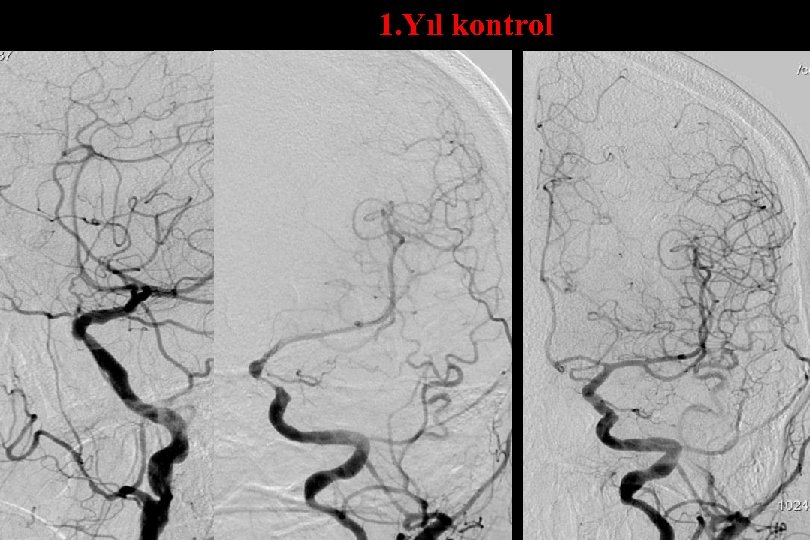

1. Yıl kontrol